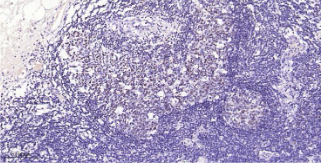

Immunohistochemical analysis of paraffin embedded Human colonic lymph node tissue slide using IHC0540H (Human OCT2 Kit).

OCT-2 is a transcription factor belonging to the POU homeo-domain family that binds to the Ig gene octamer sites regulating B cell specific genes. OCT-2 protein expression is not restricted to B cells, although expression levels are much higher in these cells. OCT-2 expression is reported to be significantly greater in germinal center derived lymphomas, although other B cell lymphomas also display high levels of expression.